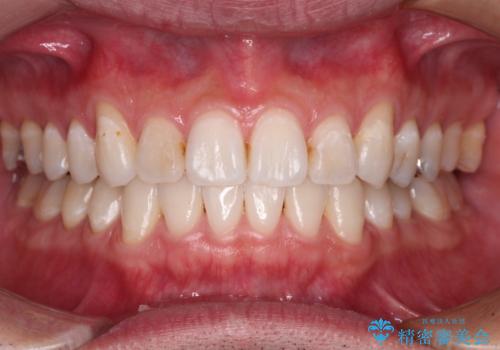

デコボコを治したい インビザラインによる矯正治療

- 前歯のデコボコを気にして来院された患者様です。

前歯が90度近く捻れていたため、しっかりと治すことを考えるとワイヤー矯正の方がおすすめではありましたが、本人の希望によりインビザラインを用いて矯正治療を行うこととしました。

途中2年強の来院がなく、改善されていたデコボコが元に戻ったり、装着時間が不足しており前歯のデコボコは十分に改善することはできませんでしたが、5年間の有効期限内で可能な限り歯列を整えることができました。